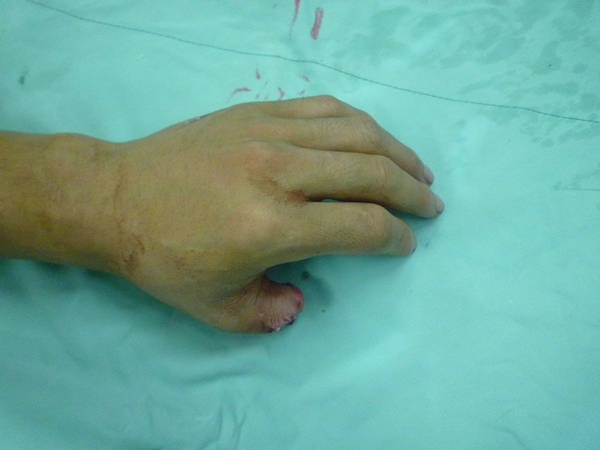

今天做的全型拇再造后供区修复的一种新方法

好久没发帖了,今天刚刚做的!供区是新的修复方式!谢谢讨论!

1个游离骨皮瓣+1个拇甲瓣+游离关节移植+1个全形再造+2处动静脉脉吻合=拇指再植。